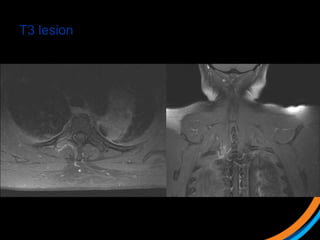

Case study 3 (Patient 009)

• 44, Female, ECOG 1

• RCC diagnosed 2007. Metastatic recurrence in 2012

• Prior RT to prevascular LN 50Gy/20# (2012)

• Started on Pazopanib, then everolimus

• Recent MRI spine shows met involving T3 and L1 vertebral body, with

involvement of superior endplate (L1)

 1) Review the images

 2) Target the lesion

T3 lesion

L1 lesion